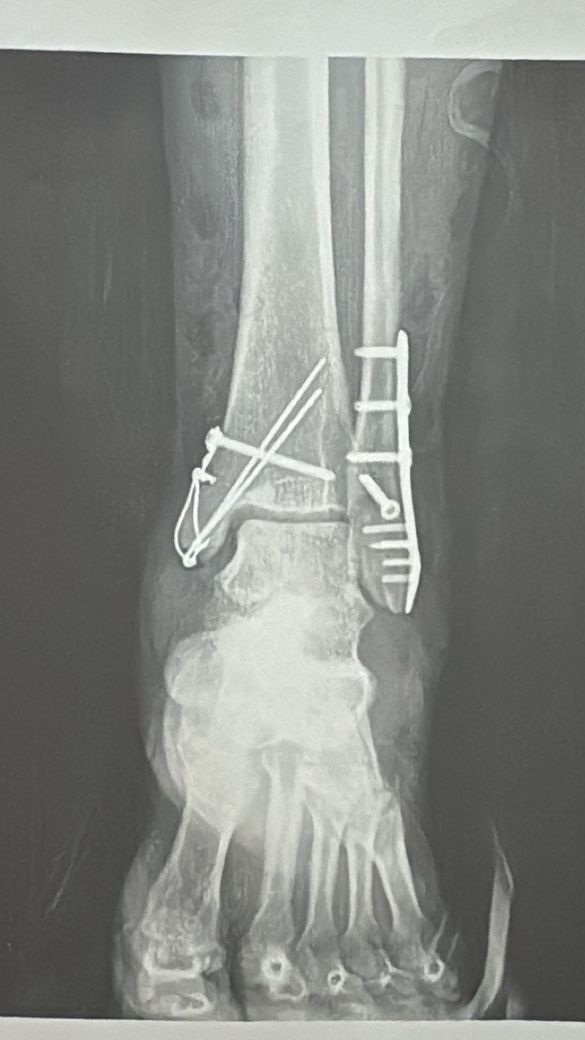

발목골절수술후 심힌 통증 및 발등 감각 둔함

발목 골절 수술을 한지 7주가 다 되어갑니다..

발목 골절수술을 하면서 연골손상 내측인데 손상 외부 근육, 힘줄 손상이 있었다고 합니다.

지금은 보조기 2주차입니다..

• 2번 째 사진